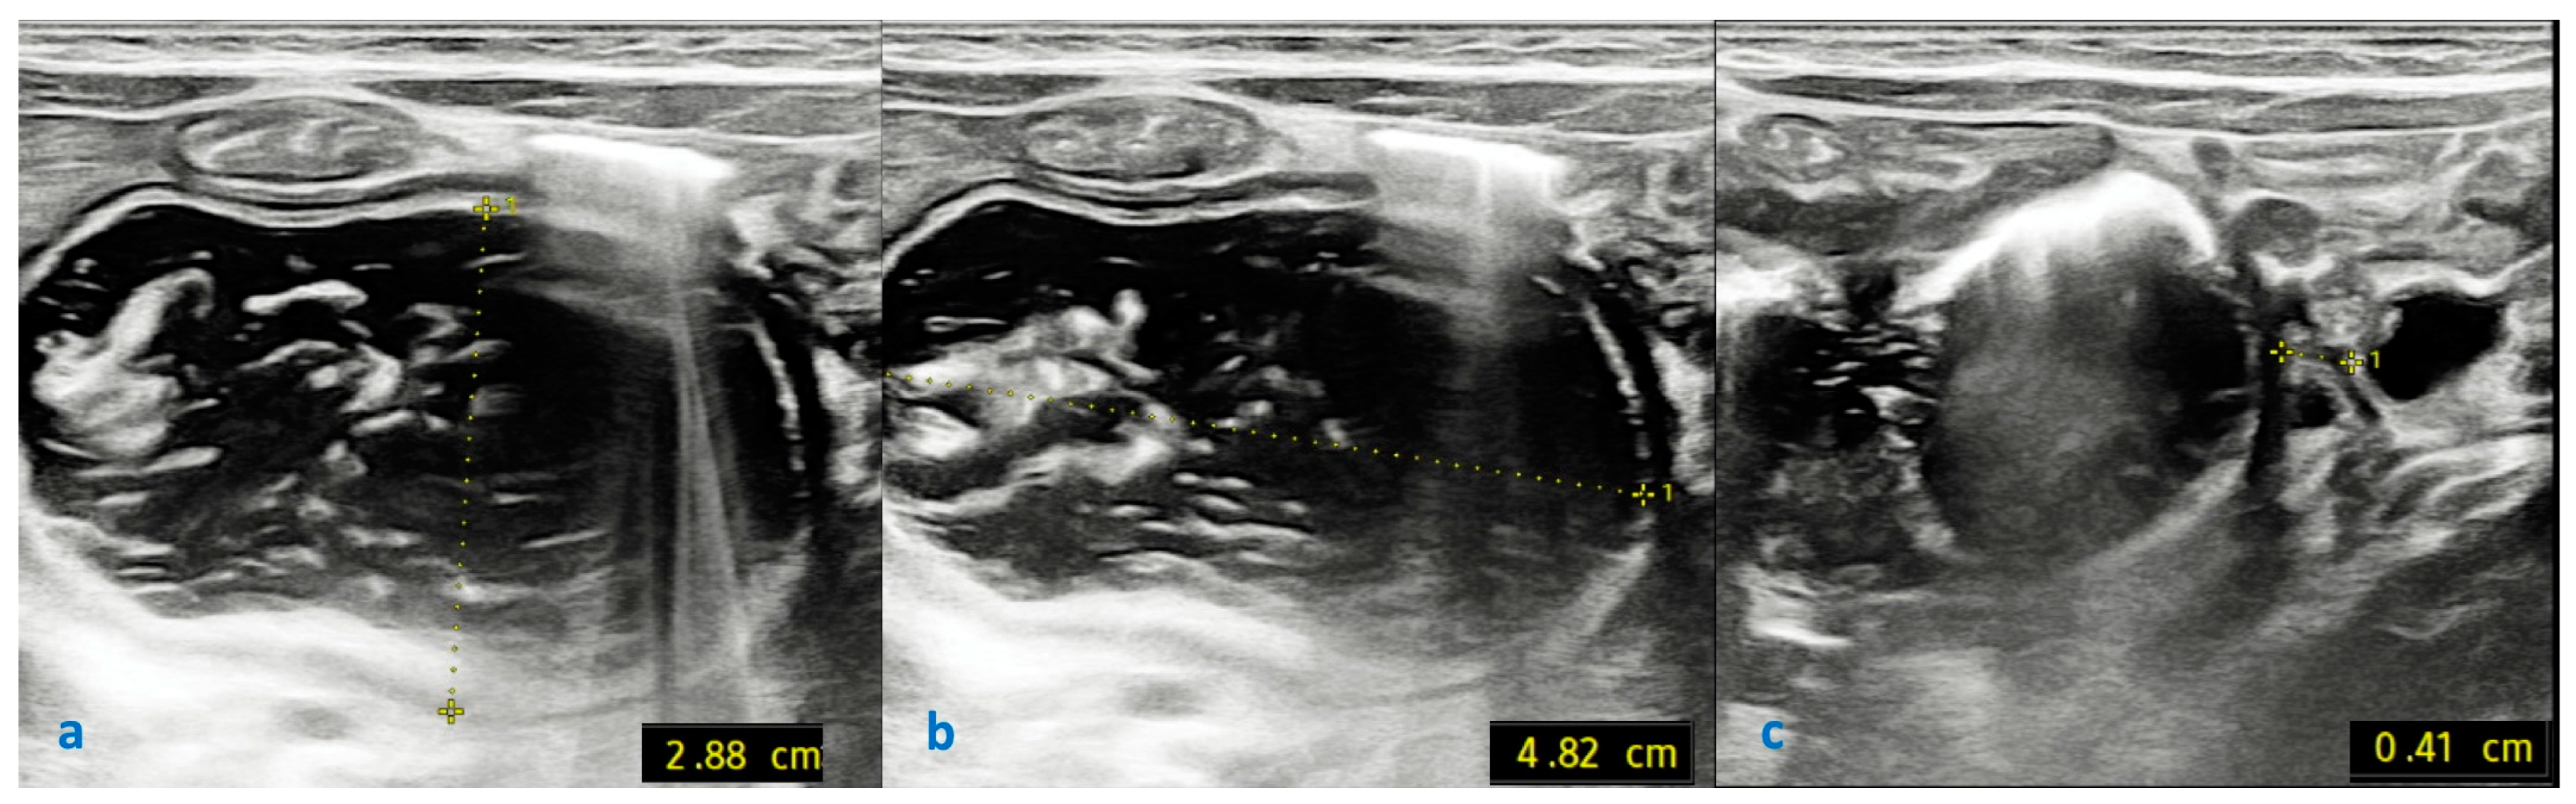

2.3. Investigations